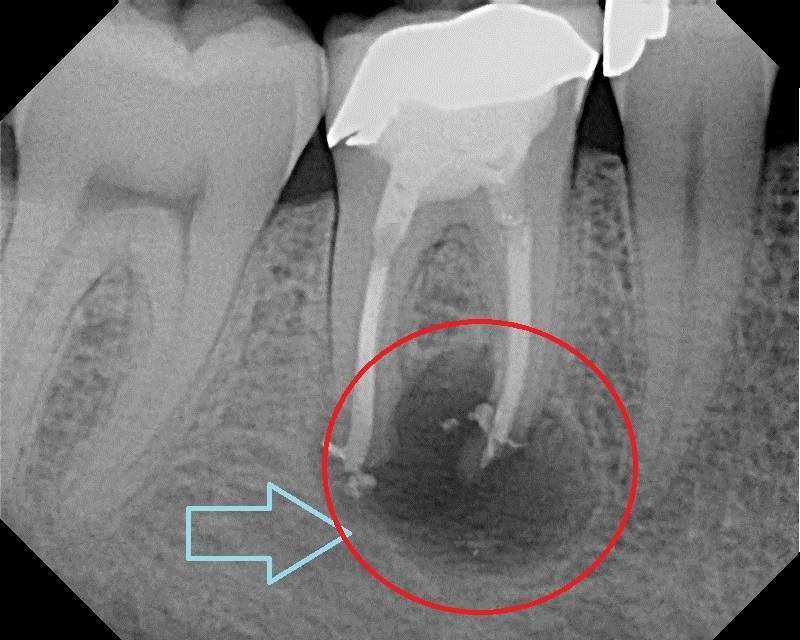

Tủy răng là phần chứa nhiều mạch máu và dây thần kinh ở phần thân răng và chân răng. Răng bị hư hỏng nặng hoặc chân răng bị viêm nhiễm đến phần tủy răng sẽ được bác sĩ chỉ định cần lấy tủy răng nhằm loại bỏ phần tủy răng bị chết hoặc hoại tử ra khỏi mô răng. Tùy vào mức độ viêm của tủy nhiều hay ít mà bác sĩ sẽ thực hiện lấy tủy 1 phần hoặc toàn phần. Việc này sẽ giúp giảm đau nhức và bảo toàn tối đa răng thật khi bọc răng sứ. Ngoài ra, việc điều trị tủy răng còn có tác dụng ngăn ngừa vi khuẩn gây viêm nang, áp xe răng và vi khuẩn lây lan sang các răng bên cạnh.

Hình ảnh răng sâu tủy răng